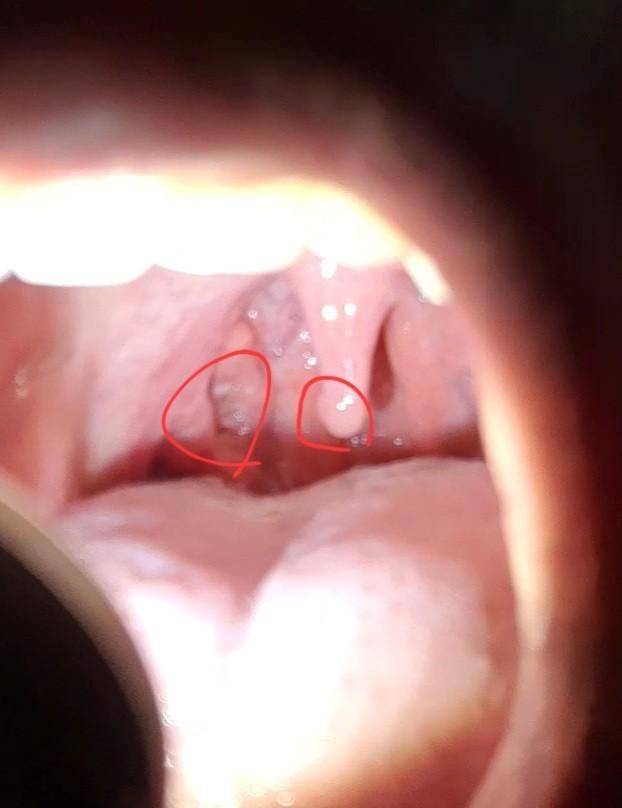

편도암이나 편도염인지 궁금합니다.

목젖(빨간원)에 물집같아보이는건 낭종이라고 종합병원 가보라고 진료의뢰서(입인두의 기타 부분의 양성신생물, Lt(D105) 써주셨는데, 왼쪽 빨간원부위까지는 못봐주신거 같아서 질문드립니다.

왼쪽 빨간원부위는 편도암이나 편도염인가요? 종양처럼튀어나온거같기도 하고, 그 부위에 흰색같은게 있어서 걱정됩니다. 이비인후과 다시 가봐야하나요?

• 우려스럽고 걱정되시겠지만 외관적인 소견만 놓고 구체적인 감별 진단을 하는 것은 가능하지 않습니다. 그렇기 때문에 필요에 따라서 조직검사 등 추가적인 평가를 받아보시라고 상급 병원을 소개해주었을 것으로 사료됩니다. 일단은 종합병원급 이상의 이비인후과에서 진료 및 정밀 검사를 받아보시어 감별 진단을 진행해보는 것이 필요해 보입니다.